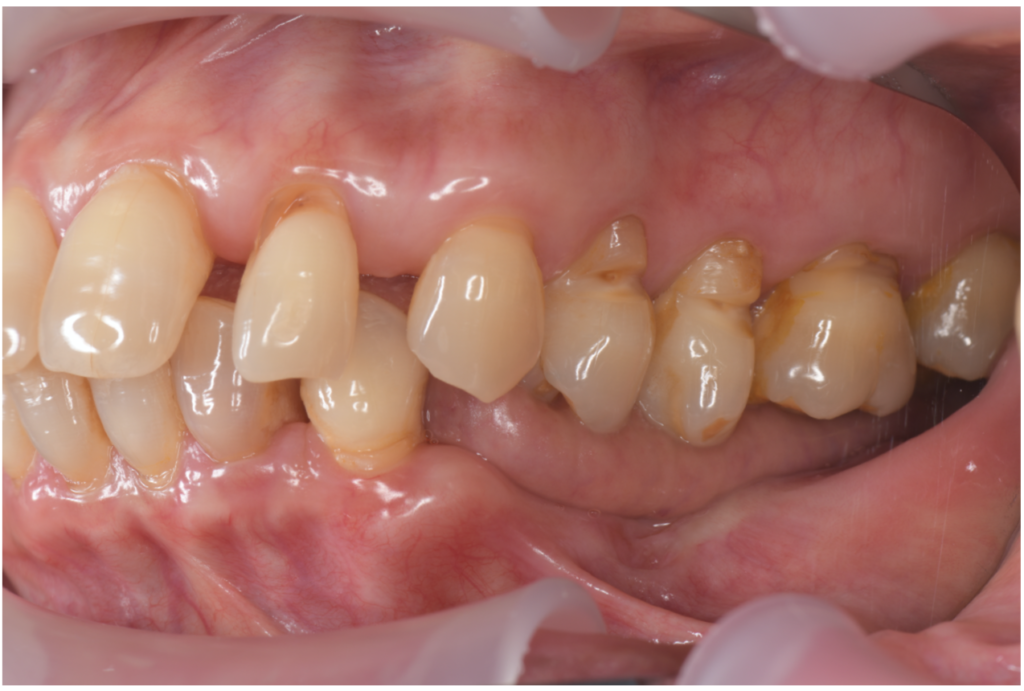

全顎治療

全顎治療(フルマウス治療)では、歯の健康だけではなく、見た目の美しさも重視しております。